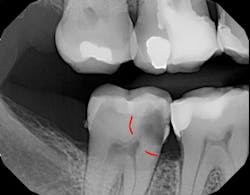

Figure 1 shows a large radiolucency on the mesial and a small radiolucency on the occlusal of tooth 31. Figure 2 shows an initial caries lesion on the distal pit and a leaking occlusal composite. Tooth 31 was sensitive to cold but normal to chewing, bite, and heat. Selective caries removal was used to prevent pulp exposure and preserve the marginal ridge.

A glass-hybrid (Equia Forte HT) was chosen due to its strength and similar coefficient of thermal expansion. The coefficient of thermal expansion did not stress the marginal ridge, and the remineralization characteristics of glass-hybrid prevented the need for root canal therapy.

Figure 5 is a 36-month follow-up bitewing radiograph demonstrating excellent support of the significantly undermined enamel and deposition of secondary dentin in the mesial pulp horns. Figures 6 and 7 show the occlusal and facial restorations respectively after 18 months. Notice the improvement in shade.